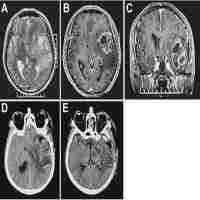

| Abstract | ObjectiveTo evaluate the rate of, reasons for, and predictors of unplanned reoperation after craniotomy for glioma in a single-institution consecutive series.MethodsPatients who underwent glioma resection at our hospital from 2015 to 2021 were included (n=1563). Multivariate logistic regression was used to examine the predictors of early unplanned cranial reoperation. The predictors that were screened included patient age, sex, tumor properties, blood loss, blood pressure and antiplatelets drugs usage.ResultsA total of 3.6% (56/1563) of the patients underwent an early unplanned reoperation after craniotomy for glioma. The reasons for early unplanned reoperation were brain edema (48.2%), cerebral infarction (33.9%) and hemorrhage (17.9%). The predictors of early unplanned reoperation were WHO grade III-IV, peritumoral edema ≥1 cm, subtotal resection, arterial/venous involvement and elevation in blood pressure ≥50 mmHg.ConclusionsGlioma properties and blood pressure management are decisive predictors of early unplanned reoperation for glioma resection. The authors provide a nuanced discussion regarding early unplanned reoperations and perioperative process improvement as a quality indicator for glioma patient populations. |